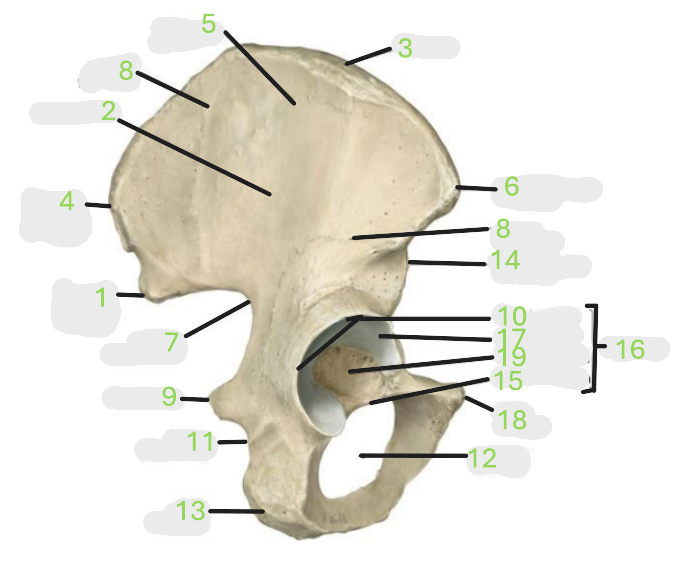

Where is the posterior inferior iliac spine

1

Where is the gluteal surface

2

Where is the iliac crest

3

Where is the posterior superior iliac spine

4

Where is the anterior gluteal line

5

Where is the anterior superior iliac spine

6

Where is the greater sciatic notch

7

Where is the inferior gluteal line

8

Where is the ischial spine

9

Where is the acetabular rim

10

Where is the lesser sciatic notch

11

Where is the obturator foramen

12

Where is the ischial tuberosity

13

Where is the anterior inferior iliac spine

14

Where is the acetabular notch

15

Where is the acetabulum

16

Where is the lunate surface

17

Where is the pubic tubercle

18

Where is the acetabular fossa

19